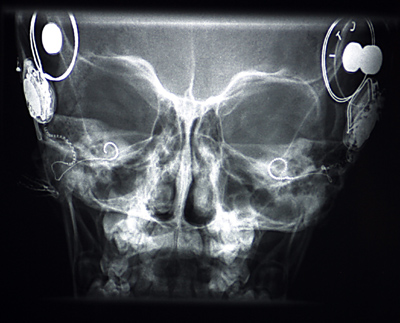

Implantatlage nach der 2. OP

Annas Meningitis lag zwar 4 Jahre zurück, aber die Gefahr der Verknöcherung bestand ja immer noch und so wurde im September 2002 eine Kernspintomographie durchgeführt, die den Grad der Verknöcherung klären sollte. Glücklicherweise zeigten die Bilder auf der rechten Seite eine noch offene Schnecke. Die Zustimmung und der Termin für die zweite OP erfolgte nach den erforderlichen Voruntersuchungen dann relativ kurzfristig.

Anna bekam ihr zweites CI am 10.12.2002 in der MHH in Hannover. Die Operation dauerte etwa 3 Stunden und verlief völlig problemlos. Die einzige Schwierigkeit, die sich während der OP ergab, war, dass der Schneckeneingang doch schon leicht verknöchert war und aufgebohrt werden musste. Das heißt, dass man eine Operation zu einem späteren Zeitpunkt möglicherweise nicht mehr erfolgreich hätte durchführen können. Der Schnitt war mit dem auf der anderen Seite von 1998 nicht vergleichbar. Er verlief nur hinter dem Ohr und die Wunde wurde geklebt anstatt genäht. Die Haare wurden auch nur ganz knapp neben dem Schnitt rasiert. Nur kurz nach dem Aufwachen, war sie für etwa eine viertel Stunde ungenießbar und brauchte so viele Schimpfwörter wie sonst in zwei Wochen nicht. Auf dem Stationszimmer hat sie dann noch etwa eine Stunde geschlafen und verlangte anschließend äußerst energisch nach was Essbarem und was zu Trinken. Normalerweise sehen es die betreuenden Schwestern nicht gerne, wenn so kurz nach einer OP gegessen oder getrunken wird, aber wir haben ihr zwei Scheiben Toastbrot und etwas Wasser gegeben, was sie dann auch mit einem Riesenappetit verspeist hat.